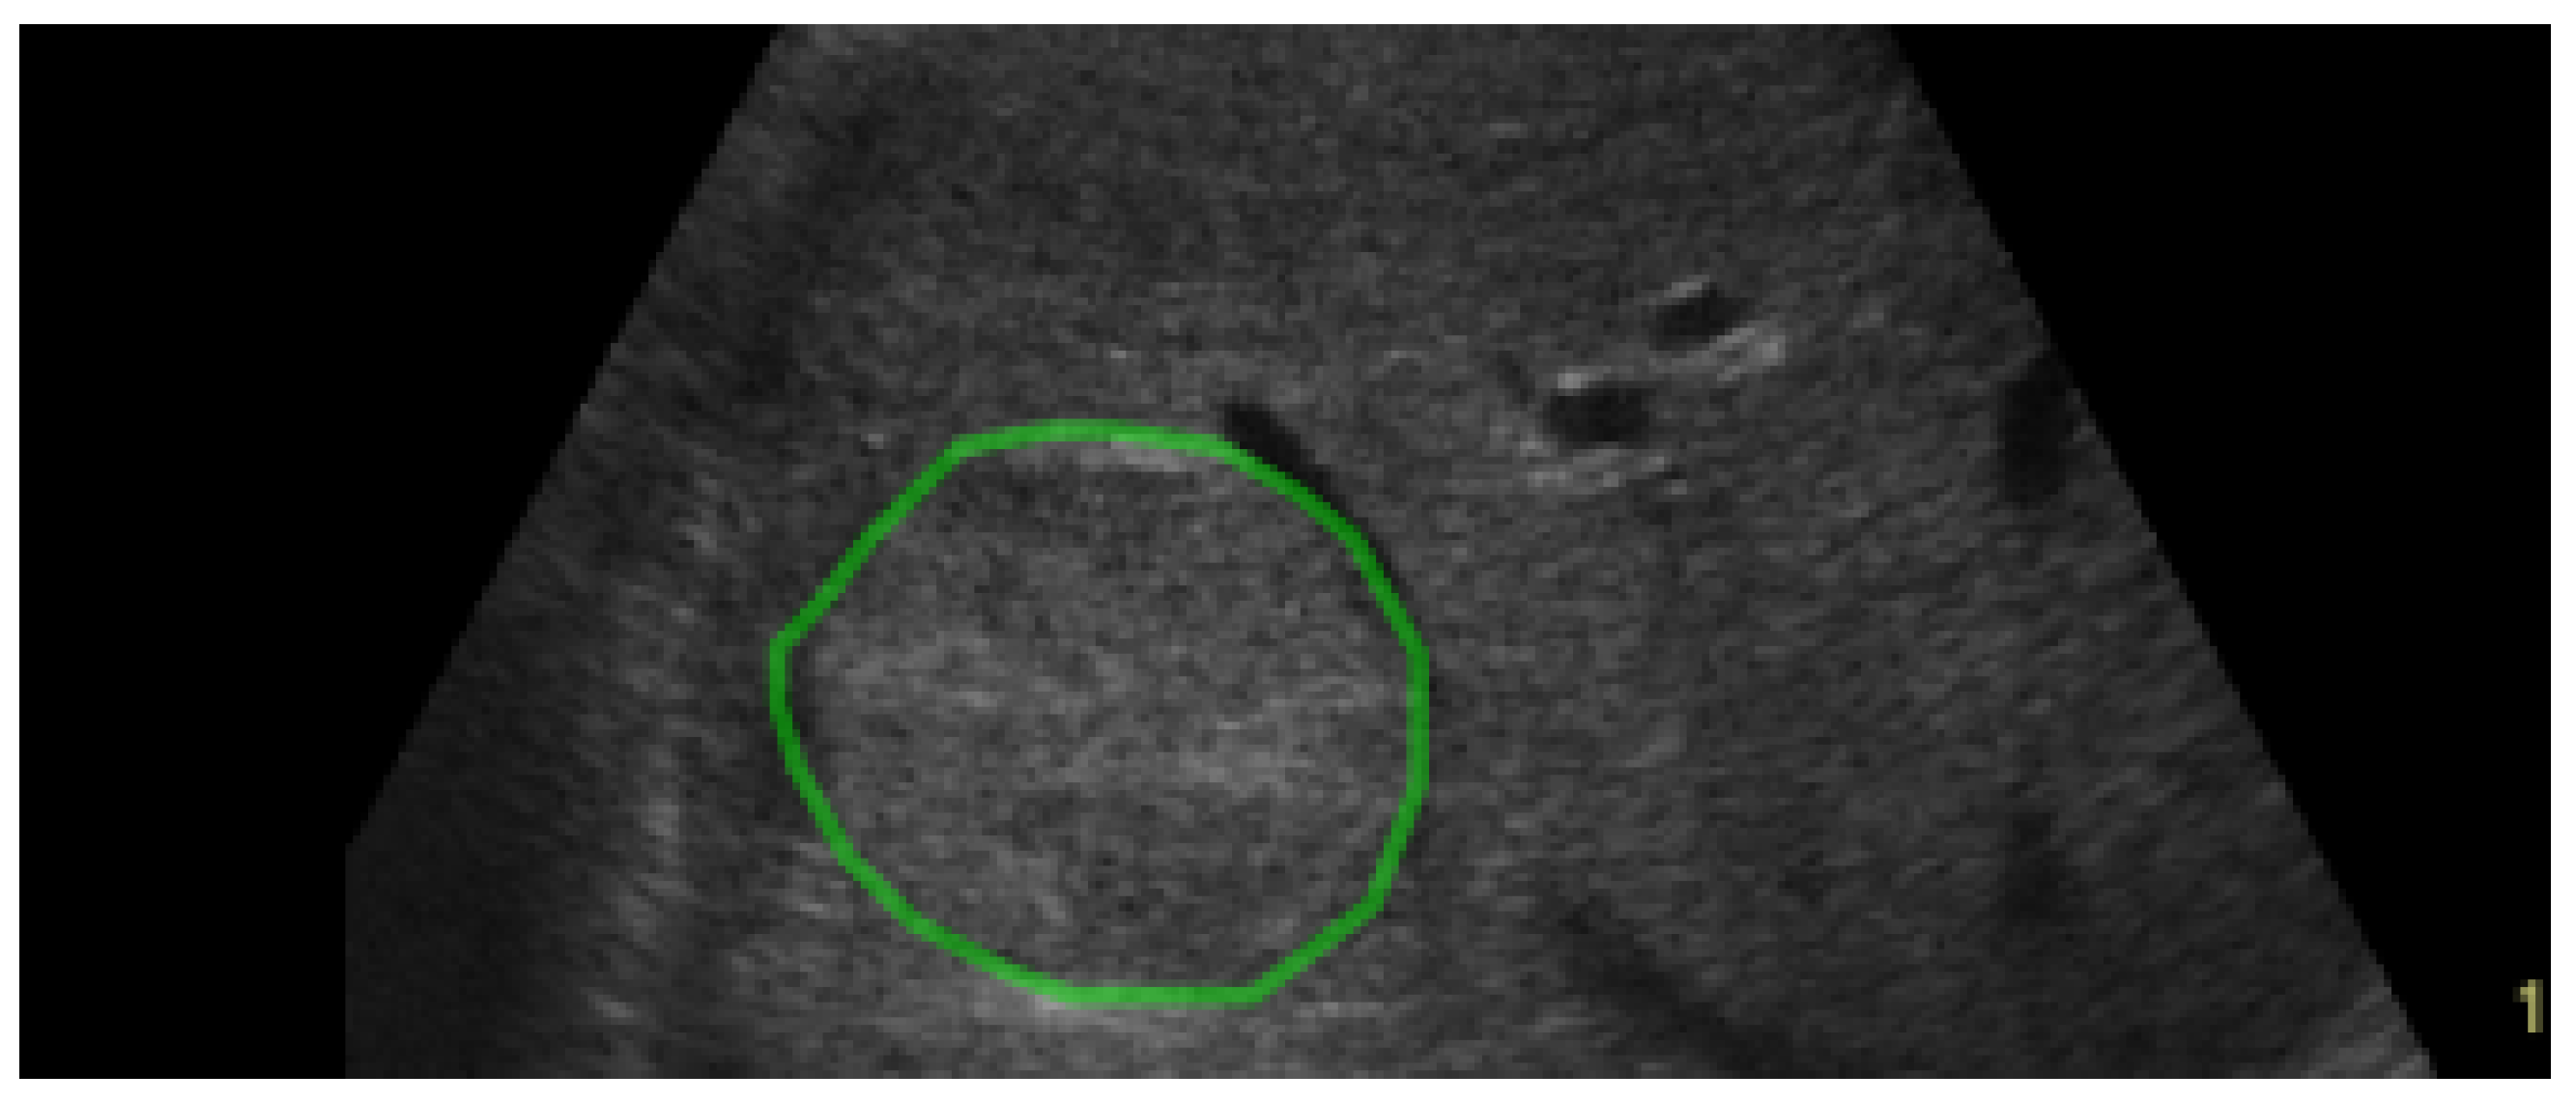

| Dataset | Class | |||

|---|---|---|---|---|

| GE7 | HCC | ![]() | ![]() | ![]() |

| PAR | ![]() | ![]() | ![]() | |

| GE9 | HCC | ![]() | ![]() | ![]() |

| PAR | ![]() | ![]() | ![]() |